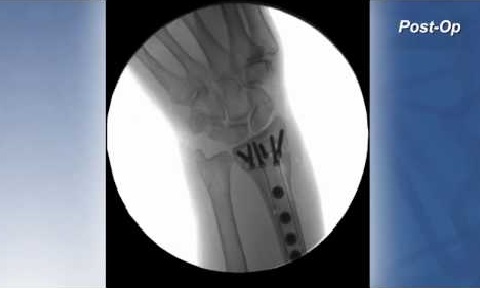

CASE STUDY Distal Radius Fracture